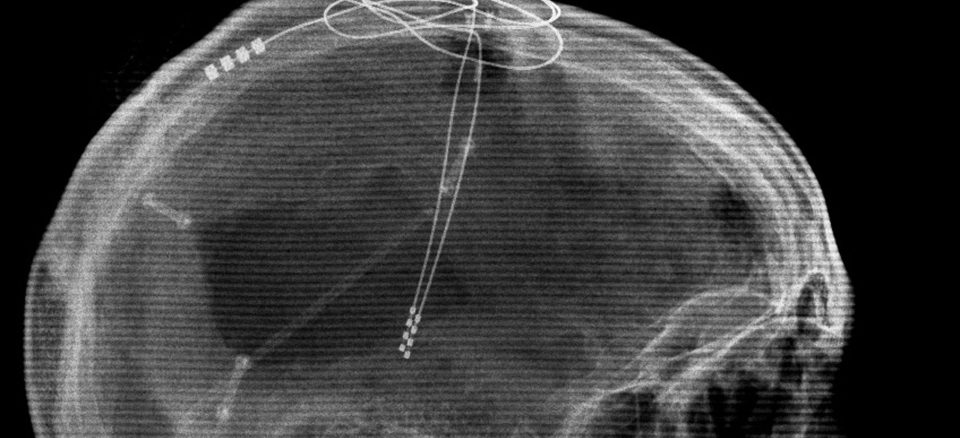

In a recent study published in The Lancet, the researchers of Toronto’s Krembil Neuroscience Centre attempted to try and stimulate an area of the brain called the corpus callosum, which is apparently a thick bundle of nerve fibres dividing the left and right sides of the brain. The area is already being used for deep stimulation to treat patients with depression. The research enlisted six women as recruit, who were suffering from anorexia nervosa, between 4 and 37 years and implanted electrodes into their brains.